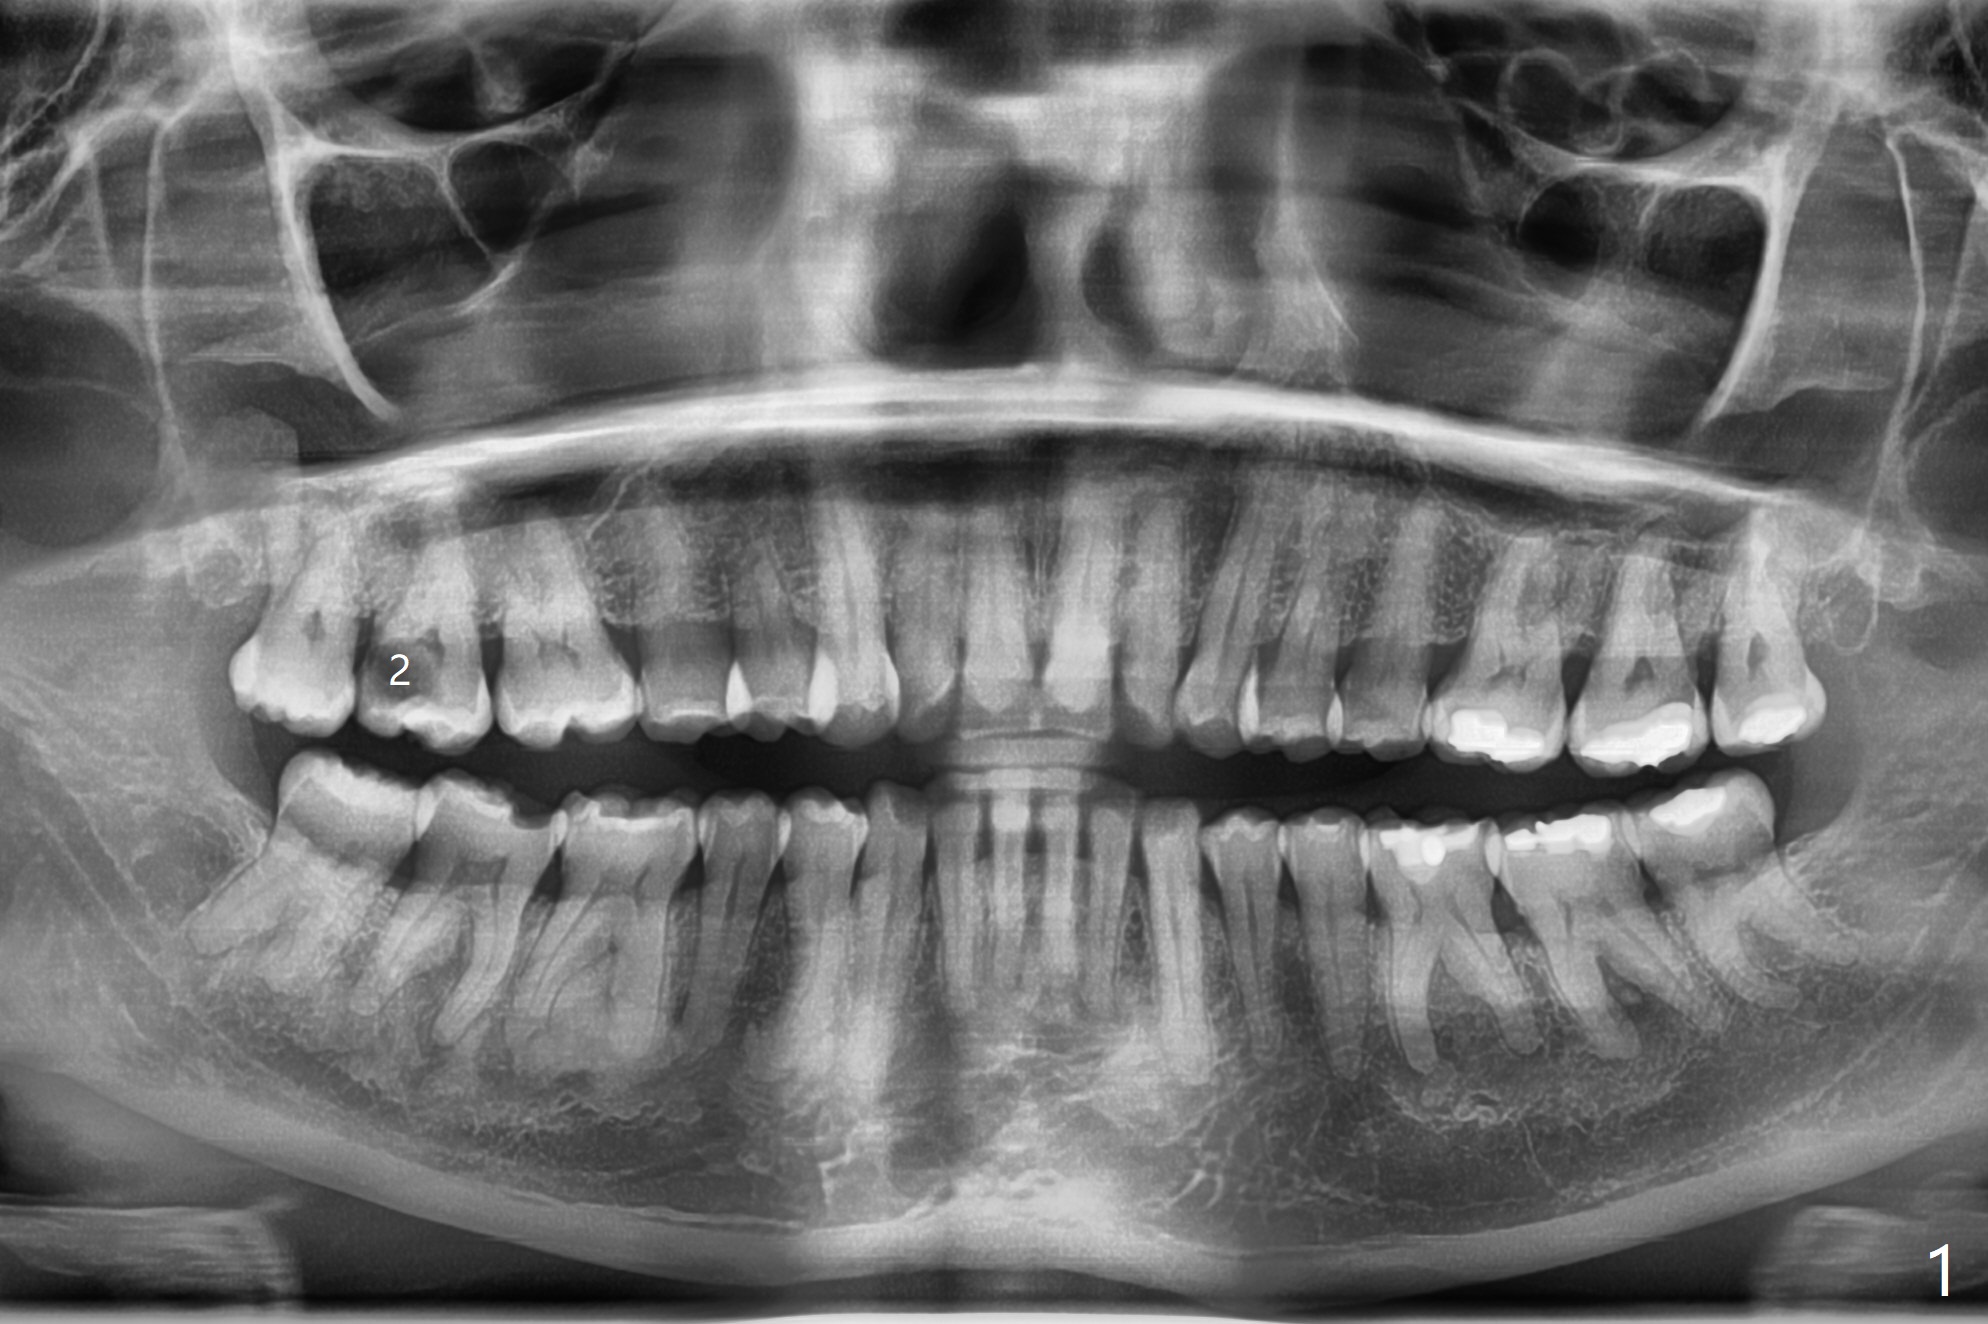

Early Socket

Healing Observation

A 49-year-old woman, a dental phobic, refuses RCT for the tooth #2 (Fig.1) and agrees with extraction. With socket preservation with allograft and Osteogen plug, the socket heals in 3 weeks (Fig.2).